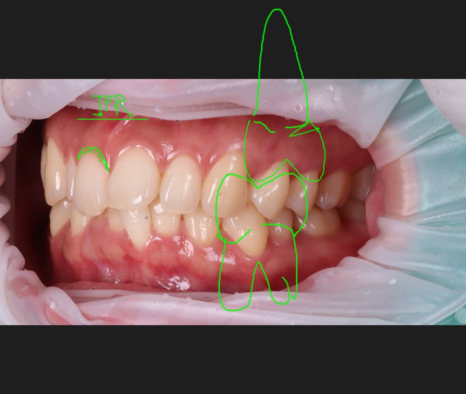

이번 환자분은 30대 여성으로 두 번째 앞니 한쪽만 왜소치였고, 더불어 가운데 앞니에 파절도 있었어요.

검진을 해보니 오른쪽 위 두 번째 앞니(측절치)는 전형적인 왜소치였고 반대편 두 번째 앞니는 크기와 형태가 정상이었어요.

문제는 치아가 ‘작다’는 사실 자체보다 양쪽의 균형이 깨져 있다는 점이었어요.

파절된 오른쪽 위 큰 앞니는 삐뚠 아래 앞니가 다물 때마다 부딪히는 형태였어요.

또, 2개 치아 모두 입천장 쪽으로 기운 형태였어요.

그 점도 감안해 바깥쪽으로 풍융하게 보이게 만들어 전체적으로 가지런하게 보일 수 있도록 계획했습니다.

왼쪽/오른쪽 첫 번째 앞니만 놓고 봤을 때, 잇몸 라인이 비대칭이어서 잇몸 성형도 같이 하는 것을 권해드렸는데요.